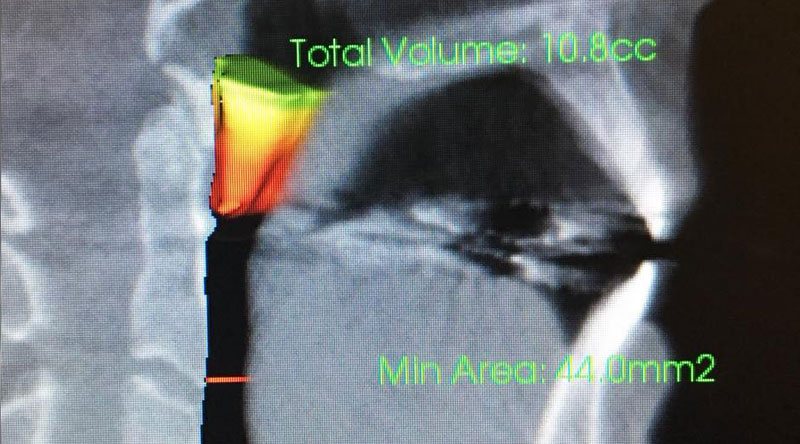

Our airway is a soft-sided tube that runs from our nose down to our lungs which allows us to bring oxygen to our body’s cells. It is important to understand that the mouth is not part of our airway. The flow through our airway changes based on the internal volume. When it comes to the airway, slight changes in volume can have a dramatic impact on the flow of air. There are multiple points where you can end up with a kink, and in many cases these kinks lead to changes in the restorative quality of our sleep. A tongue-tie is just one, albeit quite common, of these points.

When a tongue-tie creates an airway disturbance, our brains initially compensate by altering our sleep cycle to avoid the more relaxed portions of it. Over time, our brains become conditioned to the inadequate airflow, and eventually, our brains allow periods of apnea (a lack of breathing). This is the terminal stage of sleep-disordered breathing — obstructive sleep apnea — which can lead to death if left untreated.